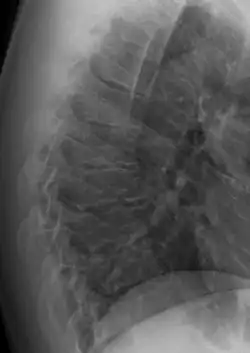

Scheuermann's disease on lateral Xray of the T spine

Diagnosis is typically by medical imaging. The degree of kyphosis can be measured by Cobb's angle and sagittal balance.